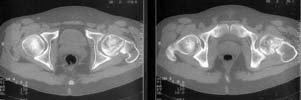

A miner 38 y.o. referred to us with 5 months old femoral neck lesion - after direct impact by a heavy construction he probably had non-displaced neck fracture. 3 months of spica cast, then non-weight-bearing. AP view and CT scan attached. Looks like AVN is present. ROM is painless and full, loading is also painless.